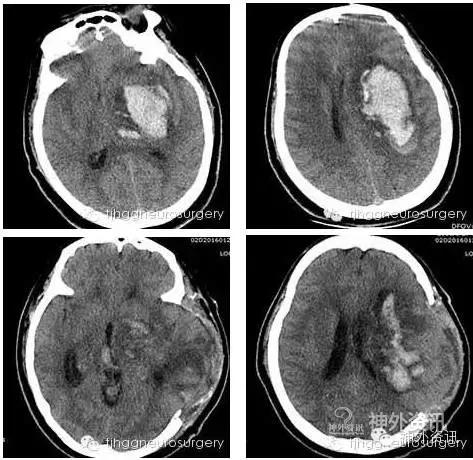

急诊CT发现颅内基底节区出血,出血量较大,同济医院急诊科医生立即请同济医院神经外科(简称“我科”)会诊,当班韩林副教授查看病人并将病人情况向上级医师雷霆教授汇报讨论后,建议行开颅脑内血肿清除术,向家属介绍病情及治疗方案后,家属表示同意,信任并接受医院做出的一切抢救安排。遂立即启动脑卒中救治绿色通道,在麻醉科、手术室的通力协作下急诊完成手术,术后患者病情逐步趋于稳定,神志逐渐恢复。家属甚为感激,考虑到仍在节期家人来回奔波多有不便,家属将病人转往离家较近的医院逐步康复。在此,我们也祝愿她早日站起来、走起来、跳起来、家麻雀摸起来!